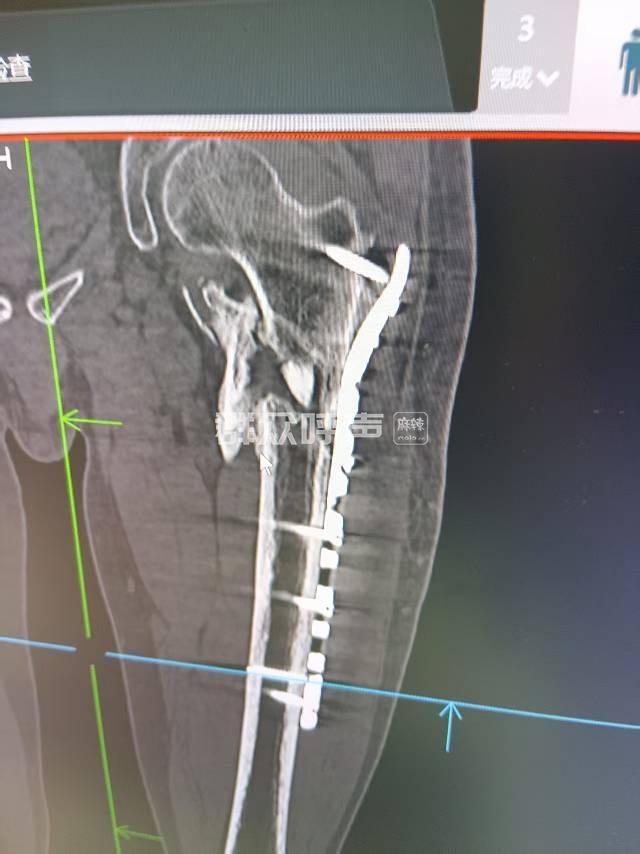

内容全是渠县人民医院王主任编的,根本上面领导没调查做好结论。有证据证明时医院写的内容

[投诉] 四川省卫生健康委员会投诉信